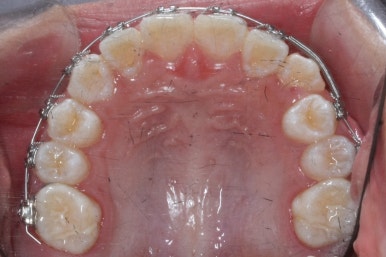

영구치도 이제 거의 다 나왔고 삐뚤한 다른 부분도 전체 메탈장치를 붙였습니다.

장치는 윗니부터 붙였습니다.

입안에 장치가 있다보니 불편할 수 있는데요. 이물감을 최소화 하고자 이동을 해야 할 양이 적은 아랫니들은 천천히 장치를 붙이기로 했습니다.

아래쪽에도 이제 장치를 전부 부착했습니다.

한 쪽의 송곳니는 제위치로 벌써 자리를 잡았네요.